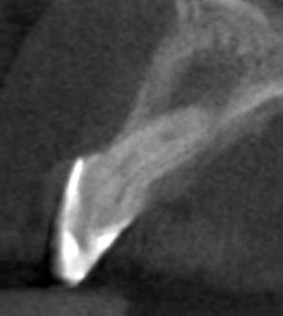

L’anomalia del dentone nella radiografia qui sopra forse è un po’ più facile da riconoscere, ma non sono comunque sicuro che tutti i dentisti sappiano di cosa si tratti e, soprattutto, abbiano idea di che trattamento eseguire.

Il fenomeno rappresentato è chiaramente un Dens Invaginatus, meglio conosciuto come Dens in Dente. In realtà esiste una terza definizione, che è quella della mia assistente Roberta che è portatrice sana di un Dancing Dente ???, che è quello che ha capito lei quando ho emesso la diagnosi guardando la rx del suo incisivo laterale di sinistra! Diagnosi che il suo vecchio dentista non aveva saputo fare…

Con tutta probabilità l’affondamento del dente da latte sulla gemma in formazione del 2.2 ha generato una deformazione dell’organo dello smalto che si è appunto invaginato all’interno della papilla dentale, formando un dens in dente, come dimostra la linea radiopaca che si intravede all’interno del dente, che non è nient’altro che smalto. Uno smalto un po’ meno mineralizzato di quello esterno, se guardiamo alla letteratura, ma pur sempre smalto.

Il primo era questo

La proprietaria del dente, una ragazzina di 16 anni, da tempo lamentava gonfiore e dolore che scompariva solo con terapie antibiotiche. Il dentista precedente aveva semplicemente corretto la forma del dente con un composito orrendo. La diagnosi non aveva saputo farla. Aveva solo saputo dire che era un dente che si poteva solo estrarre.

Con l’ausilio della Cone Beam sono riuscito a identificare che il dente aveva due canali e una radice molto palatoversa: per accedere a questi canali, separati tra loro dall’istmo di smalto invaginato, potevo fare una cavità perpendicolare al dente a livello vestibolare e una palatina.